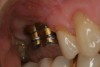

To begin, the implant fixture is uncovered, preferably with the use of a diode laser. A stock abutment that can be prepped is placed onto the implant fixture. A radiographic scan is taken to confirm the complete seating of the abutment. The necessary occlusal clearance, which is restorative material dependent, is marked with a notch. The interproximal clearances between the adjacent teeth are also evaluated and marked if any alteration is necessary. The abutment is then removed and modified where indicated. Once the spatial requirements are completed, cement retention undercuts are placed on the abutment. Using a carborundum disk or a No. 330 carbide bur, a circumferential undercut, 0.25 mm to 0.50 mm in depth, is placed toward the shoulder platform on the abutment (apical), and then another undercut is made 1 mm to 2 mm coronal to the first one (Figure 1). Depending on the implant system, sometimes the carrier, which is used to hold the implant during the surgical step, can be used in lieu of purchasing a separate abutment. One particular manufacturer uses grade 6 titanium in its carrier, which is not only compatible but also has the strength of a stock abutment. This particular carrier is designed with a large 360° undercut (Figure 2).

Fig 1. An example of two stock abutments that have been modified with apical and coronal circumferential undercuts.

Figure 1